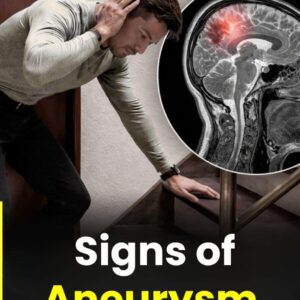

War:ning Signs of Aneurysm in Men: What You Should Never Ignore

An aneurysm is a serious condition where a blood vessel wall weakens and bulges outward. Often, it develops without noticeable symptoms, making early recognition critical. Many people remain unaware of… CONTINUE READING